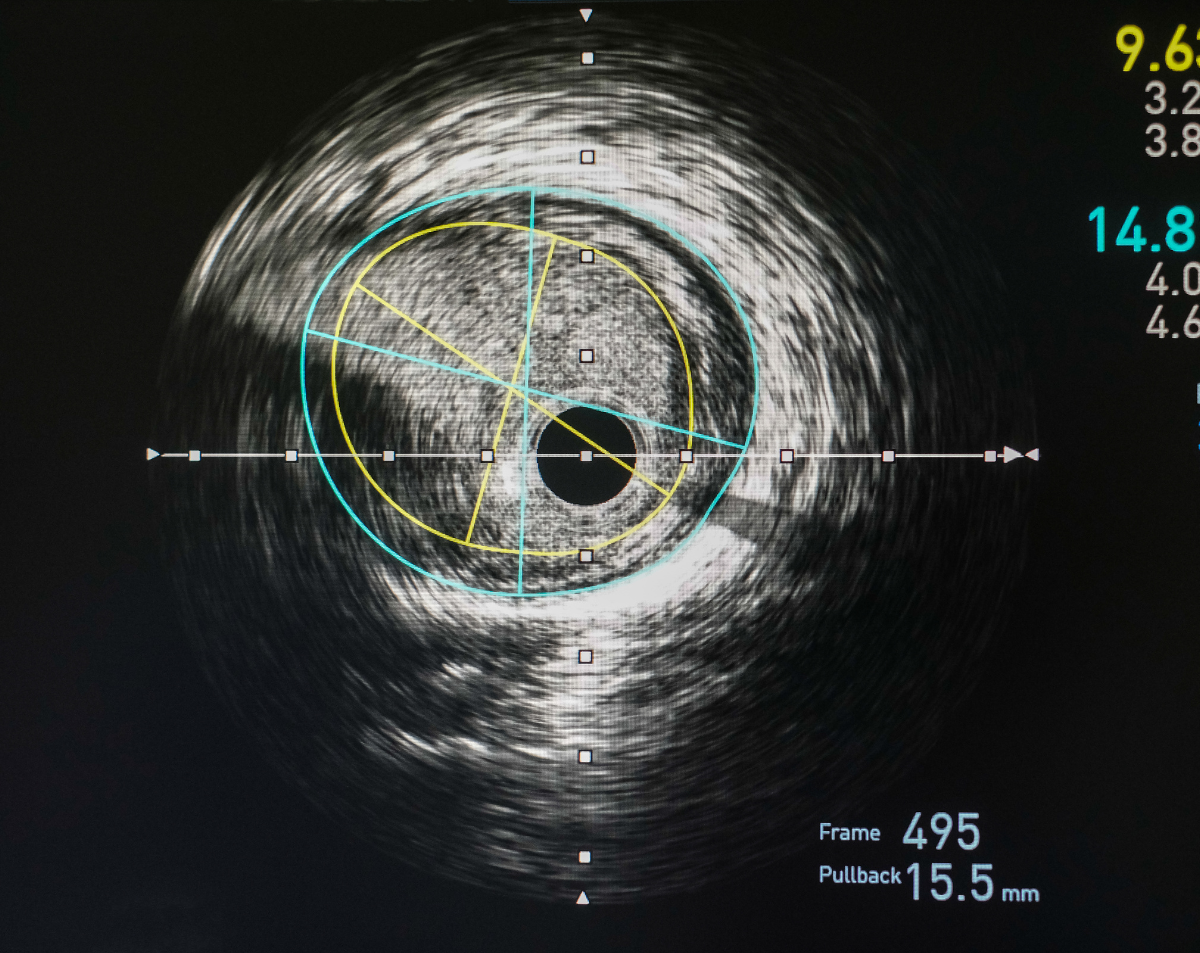

A calcium score test (also known as a coronary artery calcium score) is a non-invasive CT scan that measures the amount of calcified plaque in your coronary arteries. This test is one of the most reliable tools for detecting early signs of coronary artery disease (CAD) before symptoms like chest pain or shortness of breath appear.

Integration with Advanced Testing – Pair calcium scoring with Cleerly Health CCTA for even deeper insights.